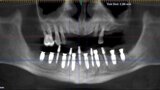

Implantacja z wykorzystaniem szablonu nawigacyjnego 3D